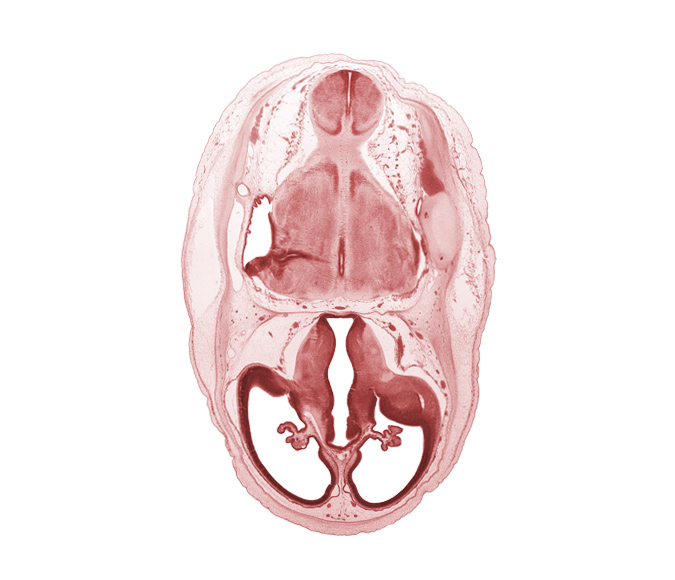

Carnegie Embryo #462 | Location: 4-03-05

Keywords: basilar artery, choroid fissure, choroid plexus, dural band for tentorium cerebelli, edge of rhombencoel (fourth ventricle), endolymphatic sac, intermediate zone, lateral ventricle, lateral ventricular eminence (telencephalon), marginal zone, myelencephalon (medulla oblongata), posterior communicating artery, pyramidal tract region, rhombencoel (fourth ventricle), roof of diencephalon, root of trigeminal nerve (CN V), stem of posterior dural venous plexus, third ventricle, ventricular zone

Source: The Virtual Human Embryo.